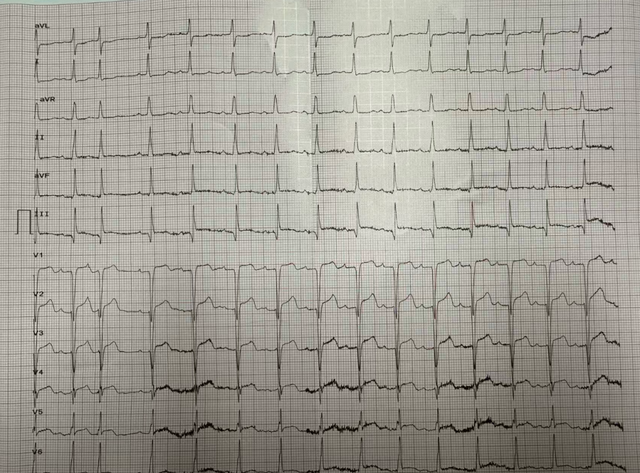

1.急性心肌梗死,入院时心功能已严重受损,心功能已达Killip III级

3.冠状动脉造影提示:心脏的三支主要血管存在严重狭窄,其中右冠脉远段完全闭塞

这意味着,在长期受多种疾病侵蚀而本就脆弱的心脏上,一条关键的“生命补给线”被突然切断,导致心肌缺血坏死,泵血功能急剧恶化,情况万分危急。